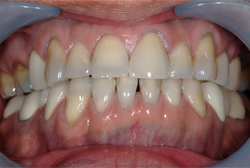

審美歯科症例 Y.Aさん(18歳女性)

治療前 治療後 上顎前歯4本をオールセラミックで修復しました。 年齢・性別 18歳 女性 治療費 440,000円(税込) 治療期間 1ヵ月 通院回数 3回 リスク・注意点 ブラッシング圧が強すぎますと、歯肉が退縮するこ […]